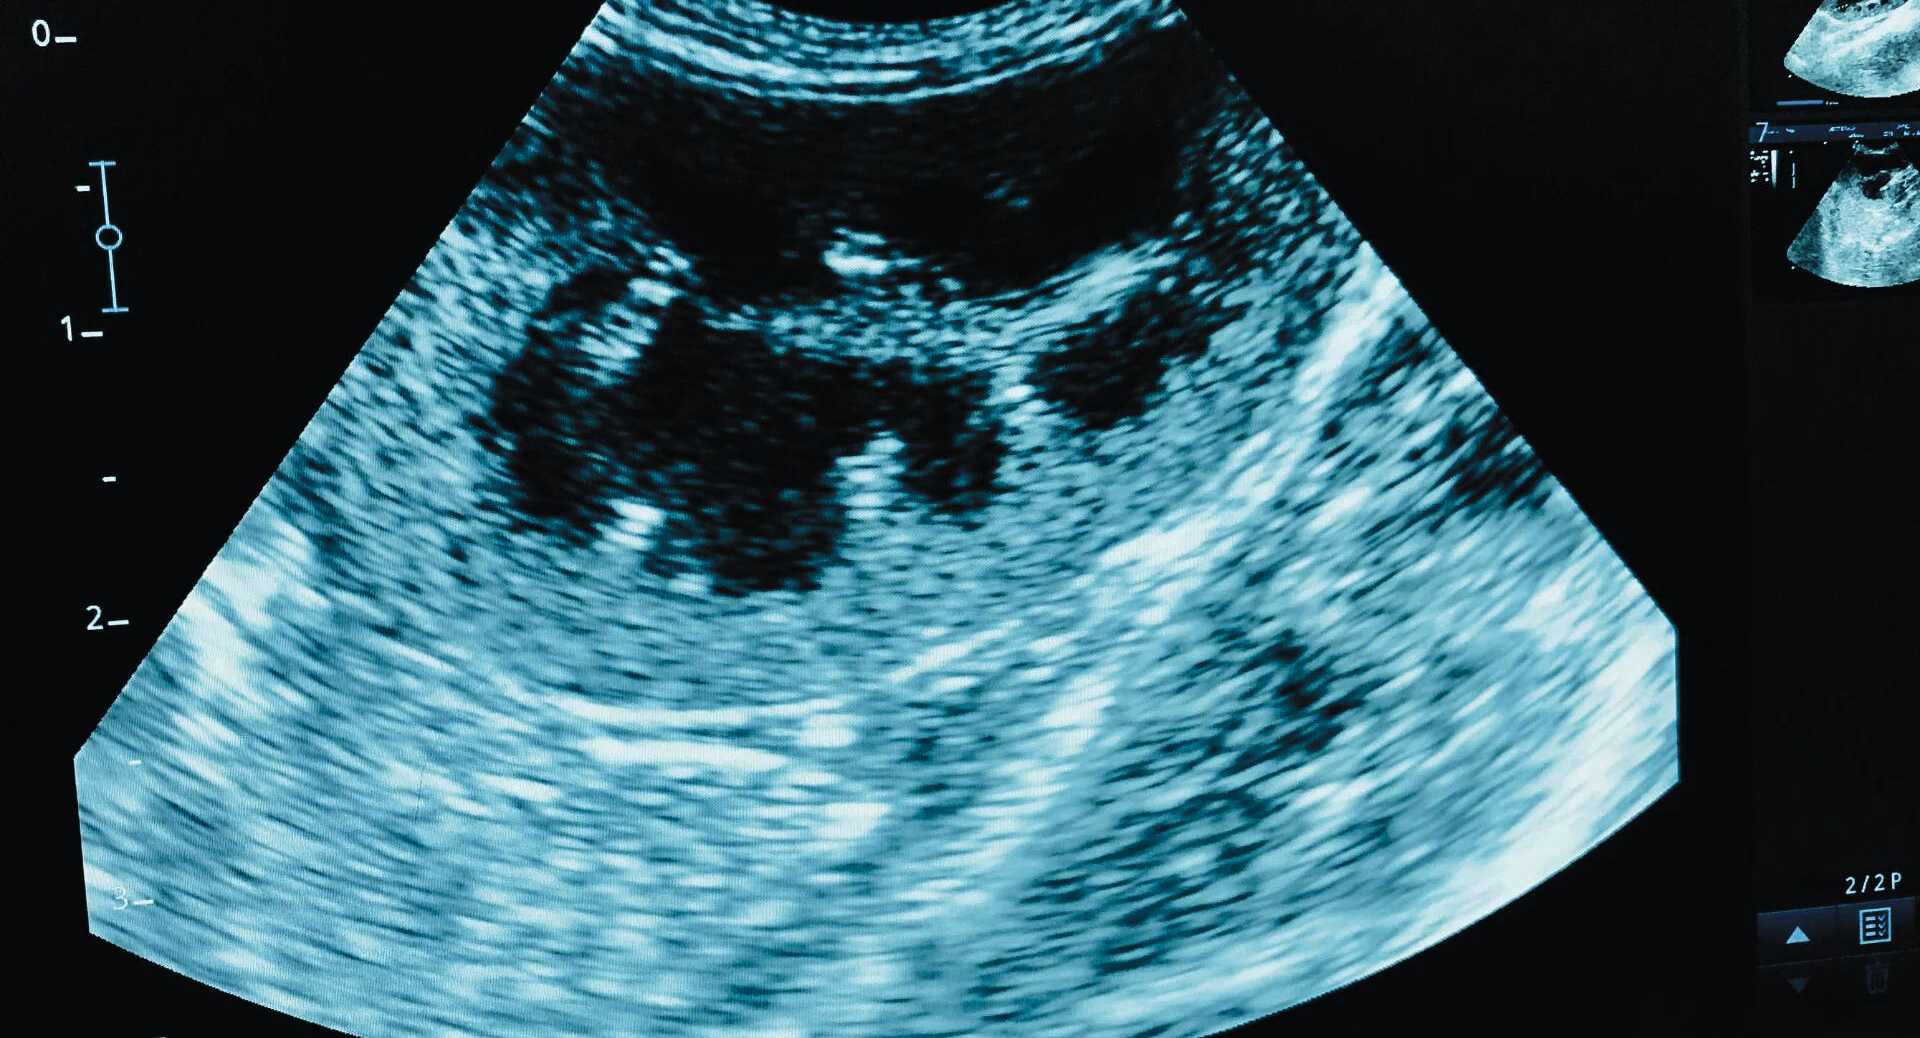

We are able to offer diagnostic services to clients at our Kingston-on-Thames practice. We have an experienced ultra-sonographer that visits our practice and uses years of experience to help image and diagnose many health conditions.